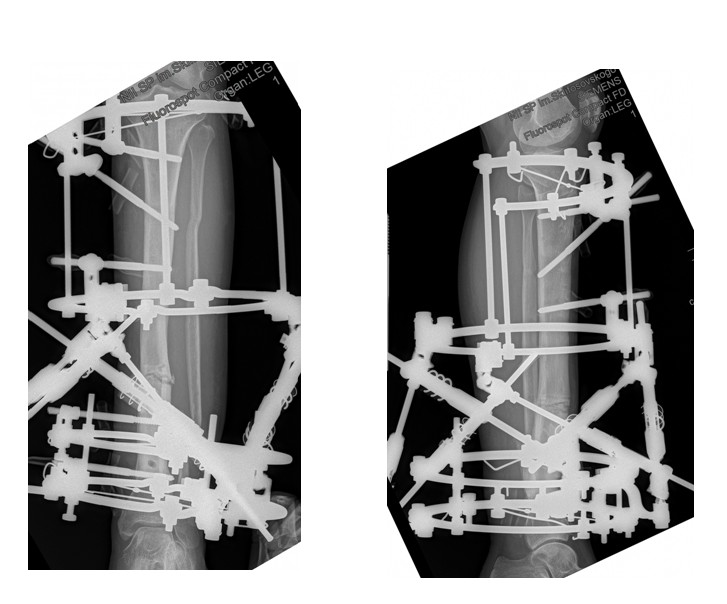

Устранение деформации с использованием пассивной компьютерной навигации